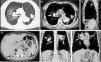

A 46-year-old man, who had worked as a sculptor for 30 years and had never smoked, was referred to the emergency department with a two-month history of productive cough, pleuritic chest pain, and progressive dyspnea. Physical examination revealed respiratory distress and digital clubbing. Laboratory tests—including complete blood count, renal function, and immunoglobulin levels—were within normal limits. High-resolution computed tomography (HRCT) of the chest revealed a right-sided pneumothorax, irregular bilateral hilar masses (Panels A and E, arrows), and mediastinal lymphadenopathy with eggshell calcifications (Panels B and E, arrows). Diffuse punctate calcifications were also observed in the spleen (Panels C and D, arrowheads). Tests for human immunodeficiency virus, histoplasma antigen, mycobacterial cultures, and GenXpert were negative. The clinical–radiological diagnosis of chronic silicosis with splenic involvement, a rare extrapulmonary manifestation, was established [1,2]. This presentation is associated with intense and prolonged exposure to silica [3,4]. The patient underwent right-sided chemical pleurodesis and started bronchodilator therapy. At follow-up, he remained clinically stable, required supplemental oxygen, and had no recurrence of pneumothorax (Fig. 1).

Chest CT scans in coronal and axial views. (Panel A) Right pneumothorax observed. (Panels B and E, arrows) show the presence of bilateral irregular calcified masses located in the hilar regions. (Panels B and F, arrows) Multiple “eggshell” calcifications of mediastinal lymph nodes. (Panels C–E arrowheads) Diffuse microcalcifications in the spleen.